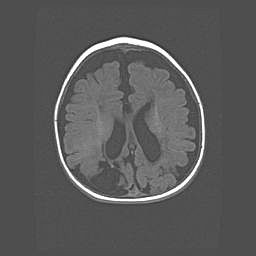

Открытая гидроцефалия.

Возраст: 6 месяцев 15 дней

Вес: 6200 г

Пол: женский

Окружность головы: 41 см

Срок гестации: 38 недель

Гидроцефалия головного мозга у новорожденных – это скопление избыточного количества цереброспинальной жидкости в головном мозге. Ее избыточное скопление в мозге приводит к патологическому расширению желудочков мозга (четырех полостей, расположенных в глубине белого вещества мозга, заполненных цереброспинальной жидкостью и связанных узкими проходами).

Открытый тип гидроцефалии (сообщающаяся) наблюдается тогда, когда нарушен механизм всасывания ликвора в системный кровоток. При этом типе причиной заболевания чаще всего является перенесенные ранее инфекции (например: менингит),  либо же наличие крови в субарахноидальном пространстве.